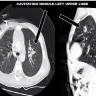

This video describes the surgical technique of performing a VATS segmentectomy in a 22-month-old child with a cavitating left upper lobe nodule.